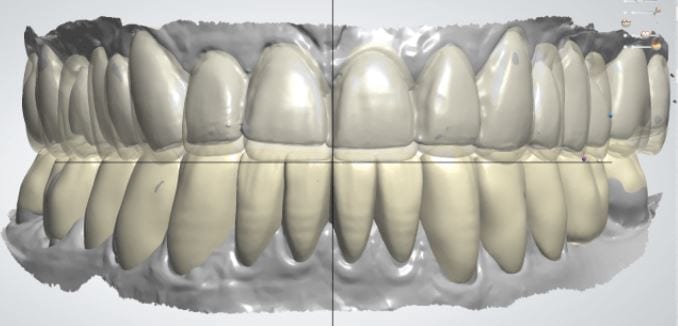

Once the appropriate library is chosen, the digital wax ups are performed. In the subsequent photos you can see the transparent overlay of the wax-ups to the original position of the existing dentition

Once the case is designed to the ideal vertical dimension then multiple shells can be fabricated for treatment. The wax up model can be uniformly reduced by .5mmm’s circumferentially and a temporary shell can be designed. Once the teeth are prepared, these shells can be relined and seated onto the preps.

Over the course of a few appointments, the vertical dimension was reduced and the temporaries were adjusted to the patient’s desires. The new upper and lower arch were captured with the Medit i500 and the jaws were related to each other.